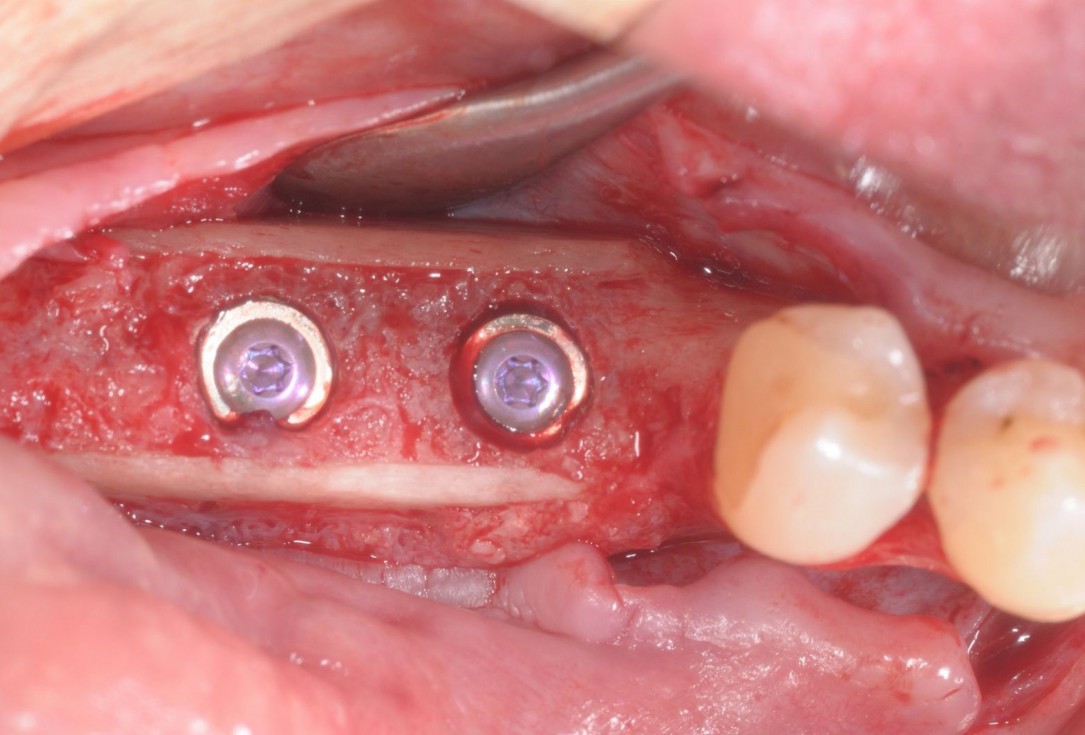

17/28 - Excellent osseous integration of the allogenic cortical plates with new bone attached to the outside and optimal bone tissue regenerationThree-dimensional augmentation with maxgraft® cortico - Dr. R. Würdinger